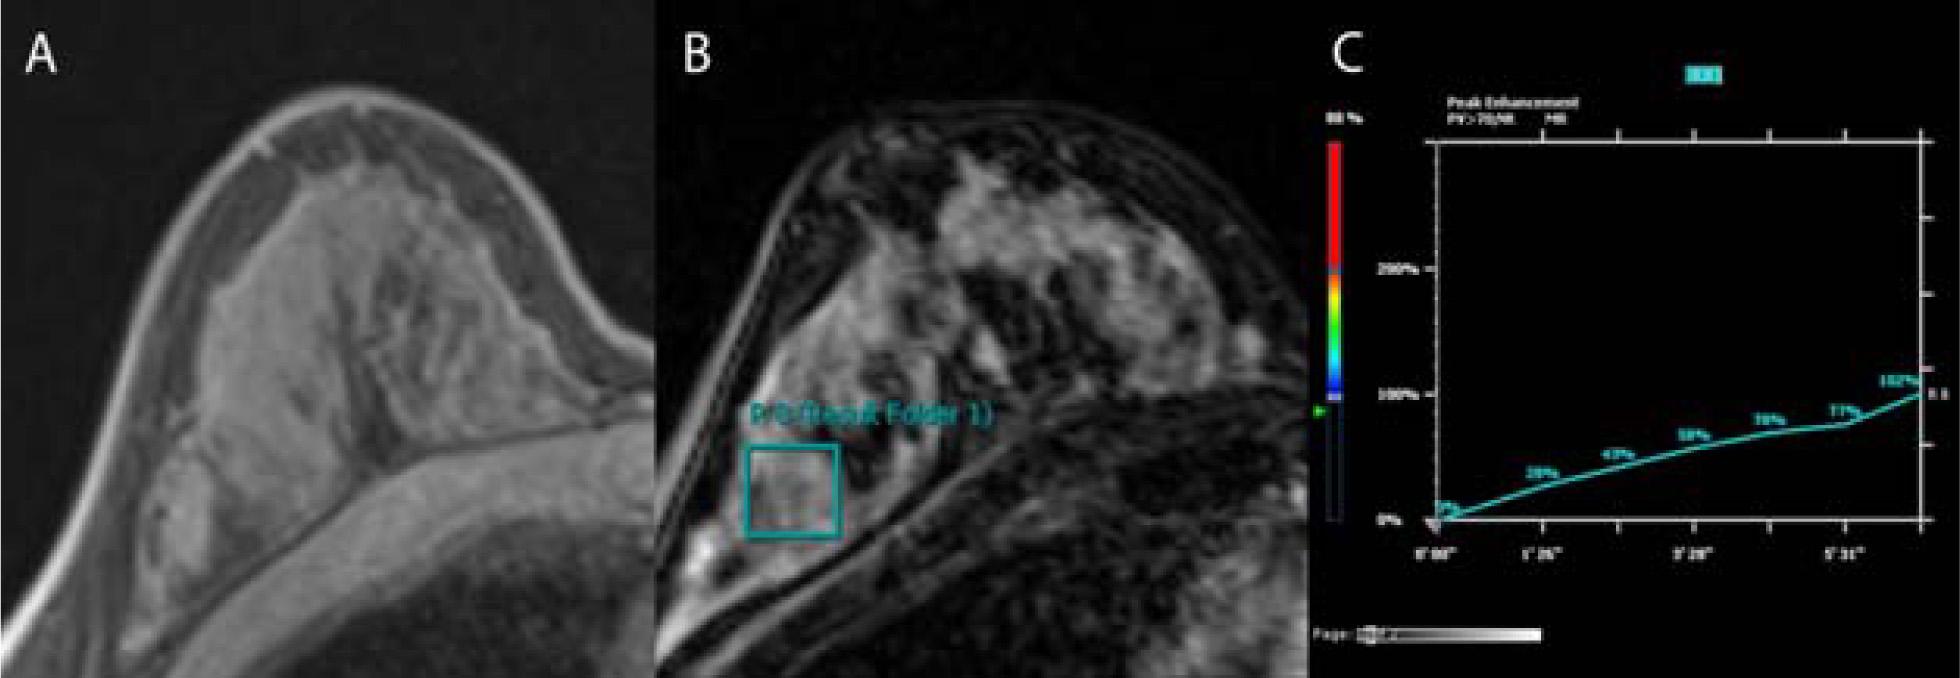

Figure 1